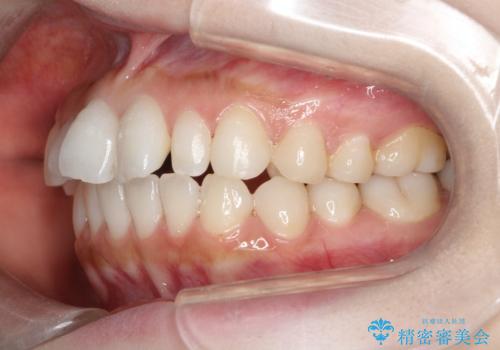

【インビザライン】矮小歯を有する方の治療②

- 前歯の凸凹を主訴に来院されました。

左上の前歯が元々小さいため、前歯の真ん中が揃わないことを伝えた上で矯正治療を開始しています。

スペースを作るために遠心移動ろIPRをおこなて治療を行いました。